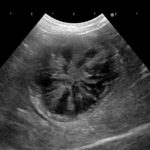

12歳のビーグルさんがかかりつけ医で定期検診をしていたところ、胆嚢粘液嚢腫が見つかりました。この病気は突然破裂し、腹膜炎を起こすリスクがあるので、内科的な管理に効果がない場合は外科的に摘除することが望ましいとされています。かかりつけの先生から破裂する前に切除して欲しいとの連絡がありましたので対応しました。超音波メスで肝臓と剥離し、胆嚢頸部をチタンクリップで処理しています。術前の超音波検査と血液検査で総胆管内の異常も認められないことから十二指腸からのアプローチは行なっておりません。術後はすぐに回復し、通常の生活に戻っています。高齢ですが頑張ってくれました。